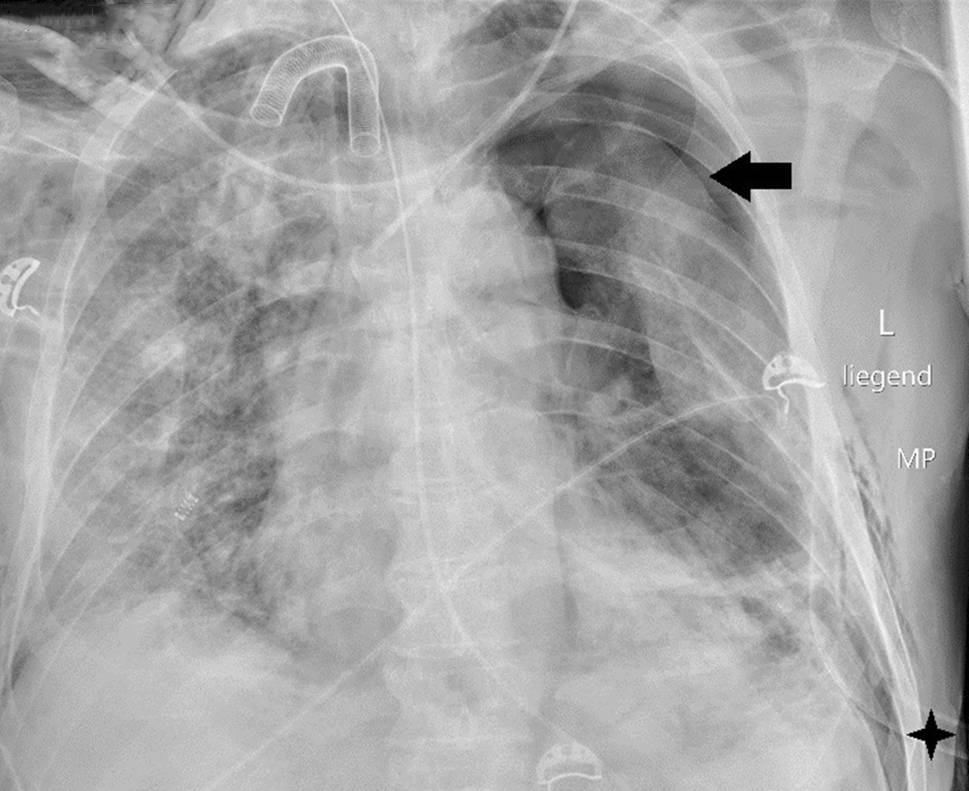

Die Kreislaufparameter waren bis auf leichte Tachykardie von 95/min unauffällig, die Patientin war afebril. Bei erhöhter Atemfrequenz von 28/min betrug die periphere Sauerstoffsättigung 87 % unter 10 l O2/min Maskenatmung. Im Labor bestanden Leukozytose von 9,5 G/l sowie Erhöhung von CRP auf 85,7 mg/l, von Ferritin auf 1062 ng/ml und von (IL)‑6 auf 225 pg/ml. In Thorax-CT zeigten sich bilaterale, diffus flächig konfluierende Milchglasverdichtungen (Abb. 7). Nach Einleitung von antibiotischer Therapie und Kortisongabe gelang es zunächst mit nichtinvasiven Beatmungsverfahren, einen Oxygenationsindex von 150 zu halten. Am Tag 6 wurden jedoch Intubation und Beatmung unumgänglich. Am Tag 13 fand sich erstmals ein Weichteilemphysem links thorakal und rechts supraklavikulär. Die Thoraxröntgenaufnahme (Abb. 8) zeigte zusätzlich zum Weichteilemphysem einen schmalen, apikalen Pneumothorax links, der umgehend drainiert wurde. Danach war das Weichteilemphysem regredient. Nach erfolgreichem Weaning von der Beatmung („dual positive airway pressure“, Spitzrendrücke 30 mbar, durchschnittlicher „driving pressure“ 15 mbar für insgesamt 19 Tage) wurde die Patientin am Tag 26 aus der Intensivbehandlung entlassen und am Tag 54 mit residualem, intermittierendem Sauerstoffbedarf von 3 l/min in die externe Rehabilitation transferiert.

Abb. 8

Weichteilemphysem (lange Pfeile), apikaler Pneumothorax links (kurze Pfeile)

Unsere Fallserie zeigt, dass sich Pneumothorax bzw. Mediastinal- und Weichteilemphysem bei SARS-CoV‑2 auf der Basis unterschiedlicher klinisch-radiologischer Verläufe entwickeln können. Bei den Patienten 1 und 2 hatten die typische Beschwerden von SARS-CoV-2 angegeben, bevor sich Dyspnoe entwickelte, die innerhalb kurzer Zeit zu fulminanter, respiratorischer Insuffizienz mit Intubations- und Beatmungsbedarf führte. In beiden Fällen waren die morphologischen Veränderungen an der Lunge ausgeprägt und diffus, der Pneumothorax nur diskret, das Pneumomediastinum dagegen stark ausgeprägt. Ein Emphysem an den Thoraxweichteilen entwickelte sich nur in einem Fall. Beide Patienten verstarben infolge der Viruserkrankung. Bei Patient 3 hatte isolierte diskrete, transiente SARS-CoV-2-Symptomatik in Form von Husten vorgelegen, trotzdem lag zum Aufnahmezeitpunkt eine gravierende, jedoch fokal akzentuierte Lungenparenchymdestruktion vor. Die Ruptur einer Pneumatozele war Ursache für Pneumothorax und eine konservativ nicht beherrschbare, pulmopleurale Fistel, nach deren chirurgischem Verschluss der weitere Verlauf günstig war. Mediastinal- bzw. Weichteilemphysem am Thorax waren nicht zu beobachten. Auch die vierte Patientin zeigte isolierte, pulmonale Symptome mit SARS-CoV-2-typischer, fulminanter Dynamik. Zum Zeitpunkt der Erstdiagnose lagen bereits ausgeprägte, diffuse bilaterale Veränderungen vor. In diesem Fall war das Emphysem in den thorakalen Weichteilen Wegweiser für die Diagnose und Therapie des Pneumothorax. Obwohl die Akutphase überlebt wurde, ist bei der Patientin mit anhaltender Beeinträchtigung zu rechnen.